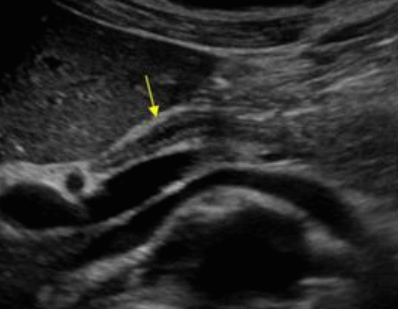

Choledocholithiasis US finding

- 총담관 내에 후방음향음영을 동반한 강한 에코가 관찰된다.

- 총담관의 확장 소견이 보인다. ( 7mm 이상)

- 담석이 관찰되지 않고 간외, 간내담관의 확장소견을 시사하는 엽총징후(shotgun sign)이나 평행관 징후(parallel channel sign)가 관찰되기도 한다.

- 엽총징후(shotgun sign): 간외 담관이 확장되어 간외 담관과 문맥이 이웃해 관찰된다.

- 평행관 징후(parallel channel sign): 간내 담관이 확장되어 인접하고 있는 문맥과 나란히 2개의 관상구조로 나타난다.